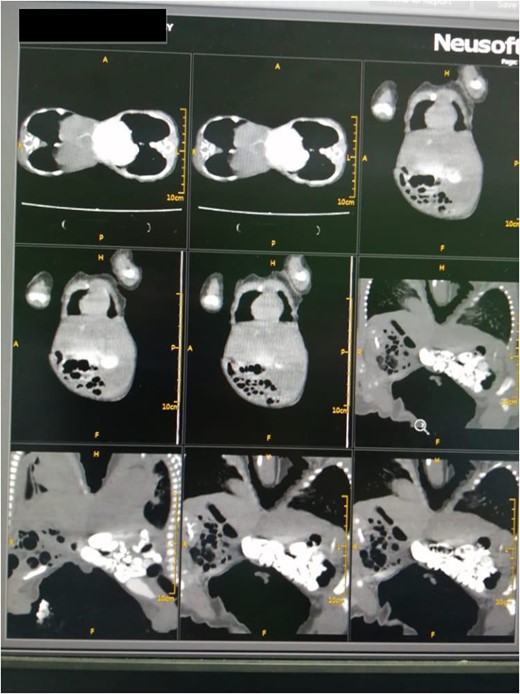

The mother was a 21-year-old female with a family history of multiple pregnancies, para three delivered uneventfully vaginally with a good outcome. Her pregnancy passed well with good antenatal care and early use of tonics, on 30 weeks the abdominal ultrasound revealed monochronic conjoined twins. At 40 weeks gestation, an emergency cesarian section was done due to labor pain, outcome was full-term, monochromic conjoined twins, cephalic, cried immediately and passed urine and meconium within 1st 24 h. On examination, both babies appeared well, not pale or jaundiced and not distressed, and weighed 2.4 kg for each one. They were fused from the xiphoid to the umbilicus with the used area covered by skin, and shared the same umbilical cord. Abdominal Computed tomography revealed a fusion of the liver through a large isthmus side by side with normal liver size and texture, no connections at the portal vein, normal vena cava and other structures (Fig. 1). other organs were entirely normal. Echocardiography showed that one twin has dextrocardia, a small restrictive Ventricular septal defect with a left to right shunt. So, the decision to elective surgical operation was made.

Abdominal computed tomography revealed a fusion of the liver through a large isthmus with normal liver and without vascular connections.